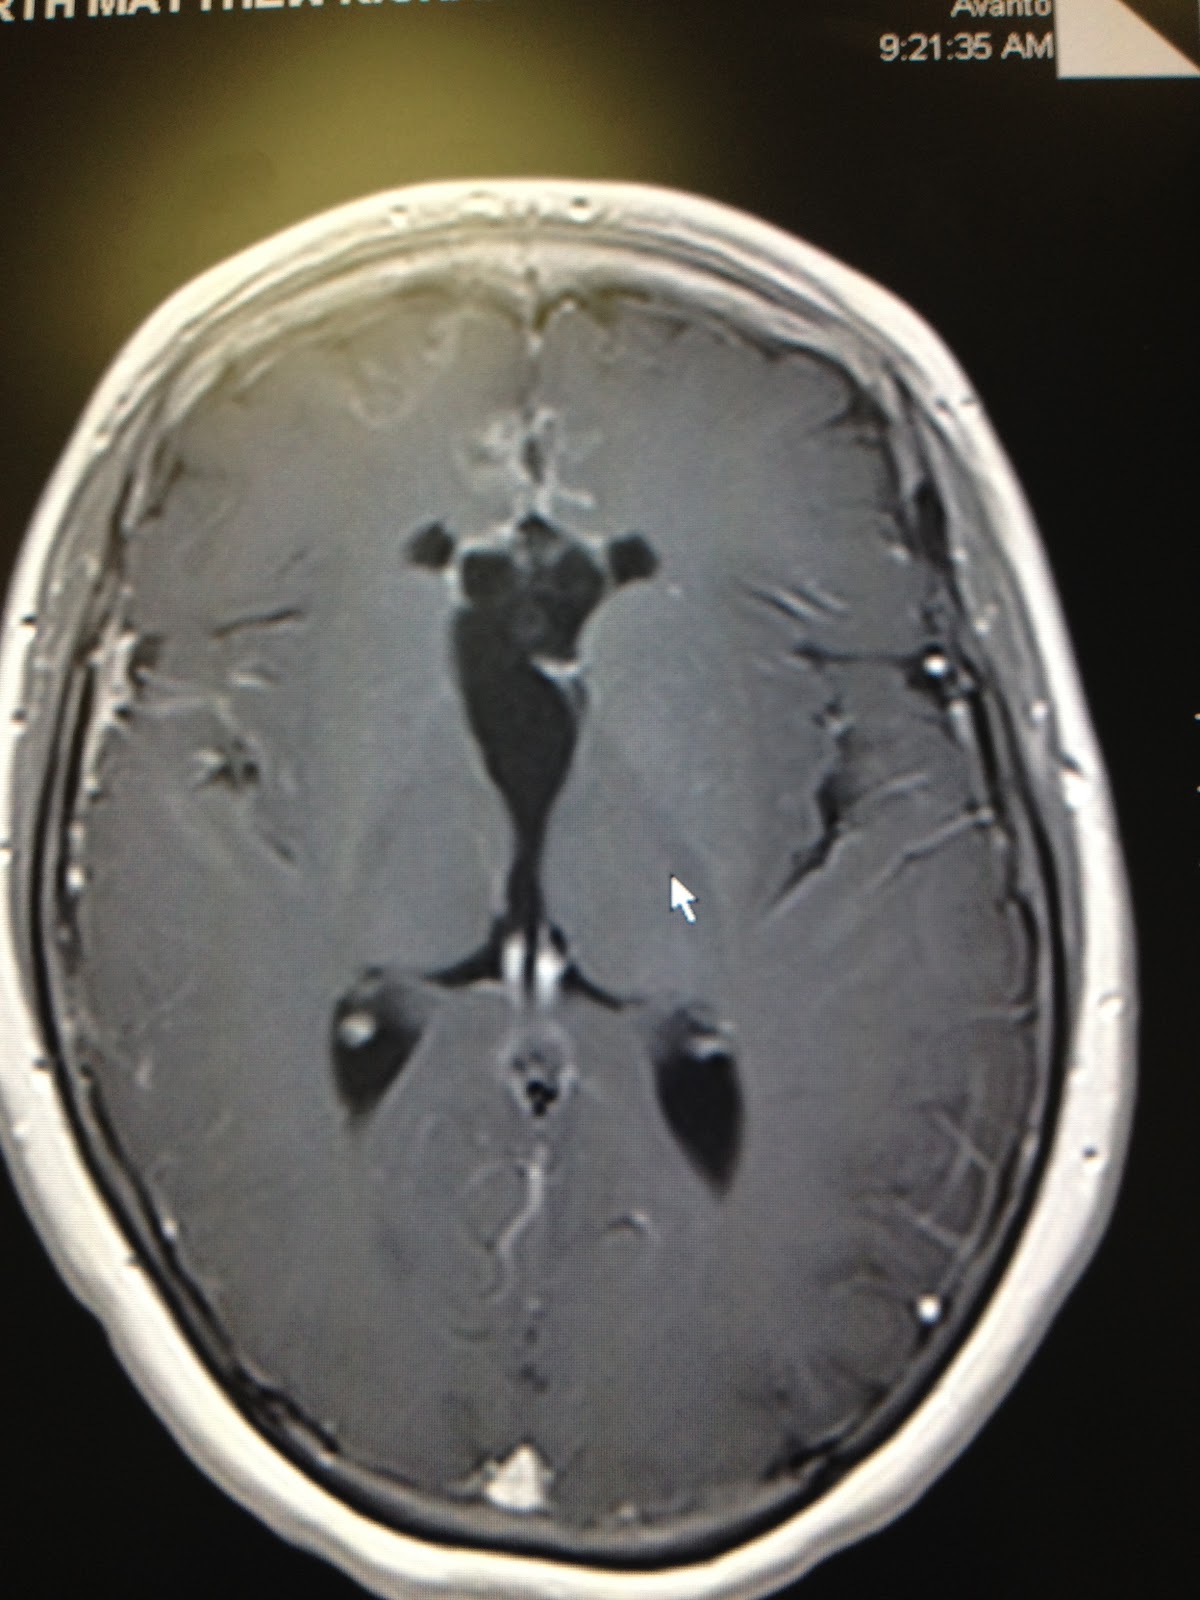

A picture is worth a thousand words, so I want to show you what research is doing to save my son.  This first scan shows his brain in November 2010.  Despite 3 years of treatment including 3 surgeries, almost 2 years of chemotherapy, and radiation, the tumor had grown larger than it had ever been.  This is a side view of Matt's head - notice his nose and face on the left of the scan.  The big white blob in the middle of the black space in the center is tumor.  All of the white snakey tendrils you see through the brain is also tumor that has spread.

This is the same side view of the tumor, taken 10 days ago when we were at St.Jude.

Here is a view looking down on his head from the top.  Again, the white blob in the center should not be there.

And here is the view from our last scans.

In this case, a picture is truly worth a thousand words.  :)